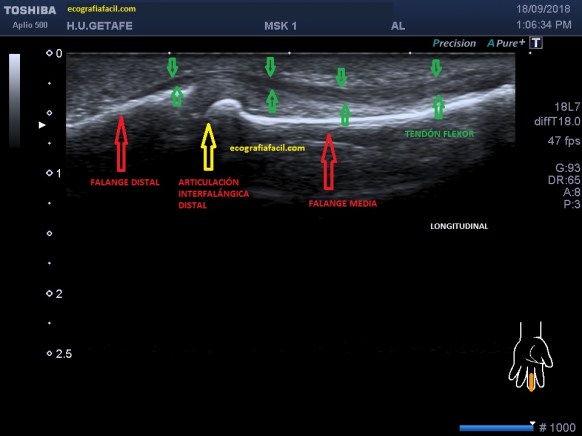

En el protocolo de exploración testicular te contaba cómo había que hacerlo y la semiología normal habitual.

Tenemos que tener claro que el testículo debe verse hiperecogénico y homogéneo y partiendo de esta premisa, realizar los cortes necesarios estudiando la anatomía testicular, incluyendo siempre, testes, epidídimo, cubierta y paquete vascular, es decir, dentro de la bolsa escrotal no nos dejamos nada sin ver.